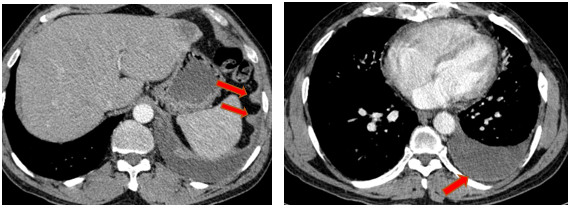

-         Chụp cắt lớp vi tính lồng ngực (08/2025): Khối rốn phổi trái ôm quanh nhánh phế quản thùy dưới trái kích thước 28x26mm, dày tổn chức kẽ vách liên tiểu thùy và nhiều nốt đặc lan tỏa khắp nhu mô, đường kính <7mm. Màng phổi trái có vài nốt đặc ngấm thuốc nốt lớn nhất kích thước 17x15mm  Khoang màng phổi trái có dịch dày 54mm. Nhiều hạch to trung thất, rốn phổi hai bên và hố thượng đòn có hoại tử trung tâm, hạch lớn nhất kích thước trục ngắn 22mm.

Hình 01: Nhiều hạch to trung thất, rốn phổi hai bên và hố thượng đòn có hoại tử trung tâm, hạch lớn nhất kích thước trục ngắn 22mm

-         Chụp cắt lớp vi tính ổ bụng (08/2025): Nhu mô gan phải có vài nốt, nốt lớn nhất hạ phân thùy VII có nốt giảm tỷ trọng, ngấm thuốc kém sau tiêm đường kính 24mm, hạ phân thùy II, III có nốt 2 giảm tỷ trọng đường kính 13mm và 27mm. Các ổ đặc xương rải rác đốt sống ngực thắt lưng, xương cùng và xương chậu hai bên – theo dõi tổn thương thứ phát

Hình 04: Nhu mô gan phải có vài nốt, nốt lớn nhất hạ phân thùy VII có nốt giảm tỷ trọng, ngấm thuốc kém sau tiêm đường kính 24mm, hạ phân thùy II, III có nốt 2 giảm tỷ trọng đường kính 13mm và 27mm